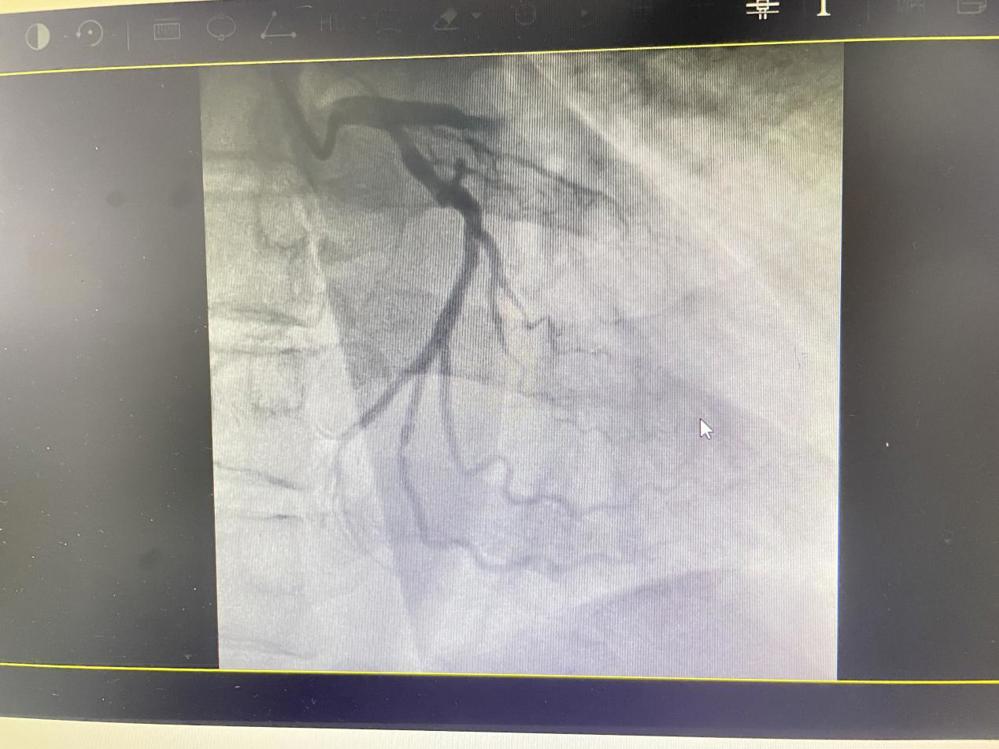

术前准备时,范叔突发室速、室颤、呼吸停止,急诊科团队临危不乱,对其给予电复律、电除颤、心肺复苏等进行抢救。范叔恢复心率后,心内科介入团队立即经右桡动脉行冠脉造影结果示:前降支近段急性闭塞,予行前降支PTCA+血栓抽吸+支架置入术。术后患者恢复自主意识,胸痛症状缓解,但是生命体征不稳定,转入ICU 进一步治疗。

未开通血管前